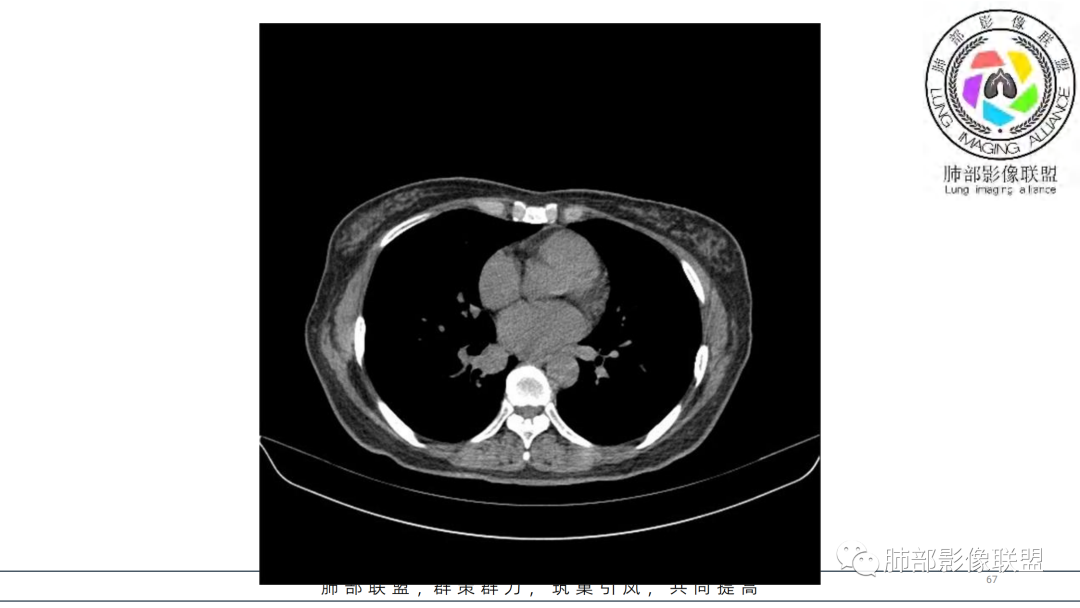

2.右肺下叶及中间段支气管后方类圆形块影,边界较清楚,未见分叶及毛刺,病灶部分突入支气管腔内(冰山一角),局部管腔狭窄,相应肺叶未见片影或体积变化。

3.块影密度均匀,未见液化坏死及钙化,渐进性强化,强化显著。

中青年女性,支气管管腔内外肿块(“冰山征”),边界较清楚,强化显著,未见阻塞性肺不张,尽管未出现“类癌综合征”临床表现,仍然符合典型类癌影像学表现。

类癌临床表现无特异性,影像学检查仍然是肺类癌的主要诊断依据。其特征性表现是孤立的、边界清楚的肿物,密度可均匀或不均匀,边缘多清楚锐利,部分病例可见浅分叶及毛刺。类癌侵及的支气管局部增厚,与正常的管壁分界清楚,局部呈乳头状突起,表面光滑。肺门旁肿块往往边缘光整、轮廓清楚、密度均匀,增强扫描大多呈均匀明显强化,可有持续强化或延迟强化。中央型肺类癌可引起支气管壁局限性增厚,形成轮廓光滑的管壁结节,并与腔外大病灶形成“冰山征”。少数病例可沿支气管腔内长轴生长,呈指套样改变,类似肺鳞癌,但较肺鳞癌血供丰富。